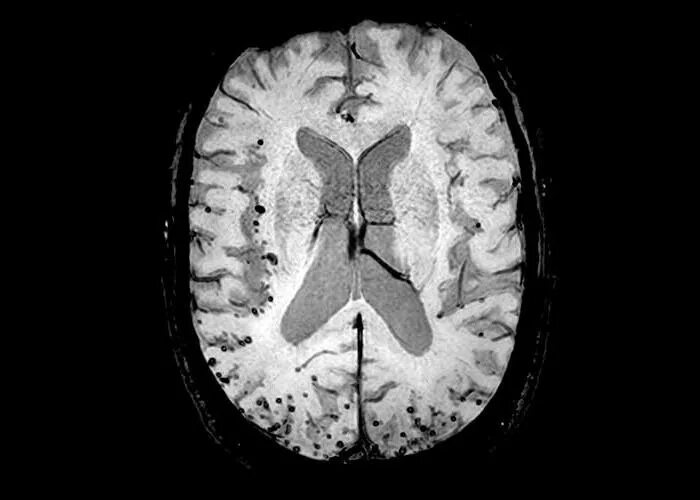

Микроангиопатия головного мозга симптомы